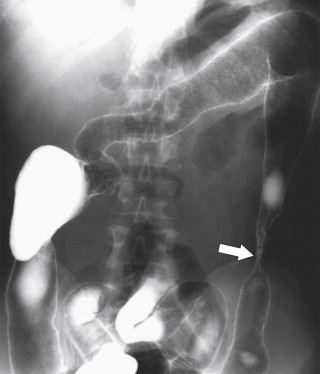

Plain radiography may demonstrate an ileus, sometimes confined to the left colon. As the disease progresses, bowel wall thickening develops ( Fig. 5-34 ) with a toxic megacolon if severe ( Fig. 5-35 ). BE is now rarely performed, but results demonstrate thickened folds and ulceration, either linear or with mucosal sloughing. Healing can lead to stricture formation ( Fig. 5-36 ). The findings are now usually made by CT and are similar to other forms of colitis (inflammatory bowel disease, infectious colitides, and radiation colitis if the radiation field included the colon). The disease is suggested in the appropriate clinical setting and by the left-sided distribution of the colonic changes ( Fig. 5-37 ). Severely affected patients show colonic pneumatosis as the gas permeates the damaged mucosa, which can then enter the mesenteric venous system and be recognized as mesenteric venous gas (particularly at CT) and ultimately intrahepatic portal venous gas. Occasionally, ischemia occurs proximal to an obstructing colonic stricture, such as colonic adenocarcinoma. The obstruction causes marked distention of the proximal colon, compromising its vascular supply or directly invading mesenteric vasculature ( Fig. 5-38 ).

Figure 5-36, BE in a 71-year-old man with a left mid-descending colon stricture ( arrow ) secondary to fibrosis from prior ischemic colitis.